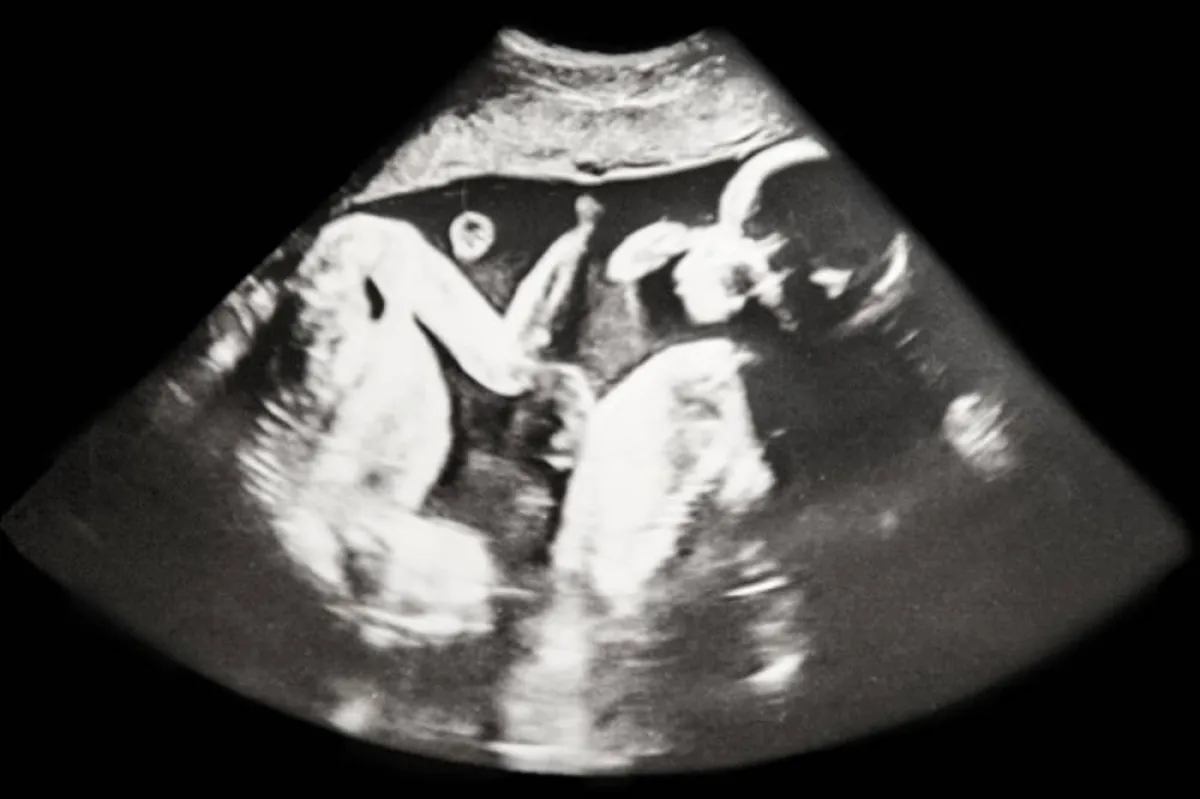

- في نهاية الشهر الرابع، يمكن أن تشعر بنبض في أكثر من موضع في الرحم في نفس الوقت، وهذا يحدث في حال لم تقم الأم بالتصوير بالسونار.

- كما أن الحامل بتوأم تشعر بحركة الأجنة في وقت أبكر من المعتاد، فغالباً ما يتحرك الجنين في نهاية الشهر الرابع، ولكن الحامل بتوأم تشعر بالحركة قبل ذلك.